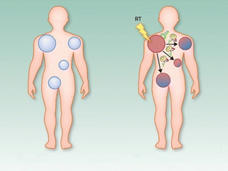

Off Target: Investigating the Abscopal Effect as a Treatment for Cancer

In people with cancer, the abscopal effect occurs when radiation—or another type of localized therapy—shrinks a targeted tumor but also causes untreated tumors in the body to shrink. Researchers are trying to better understand this phenomenon and take advantage of it to improve cancer therapy.